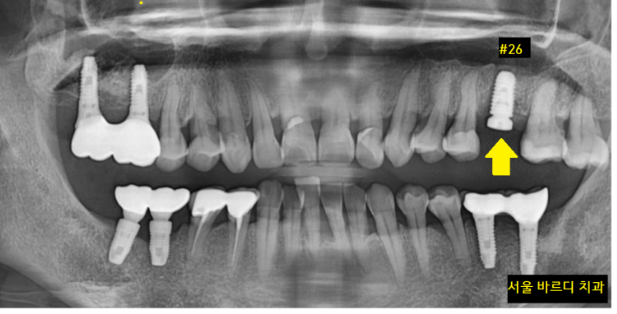

230610

3월에 염증을 긁어내고

1차 뼈이식을 진행

3개월 정도 지나 뼈가 어느 정도 찼을 때

2차 뼈이식과 미사역 임플란트를 진행하였습니다.

2차 뼈이식을 진행하면서

상악동도 들어올리는 부가적인 수술을 같이했습니다.